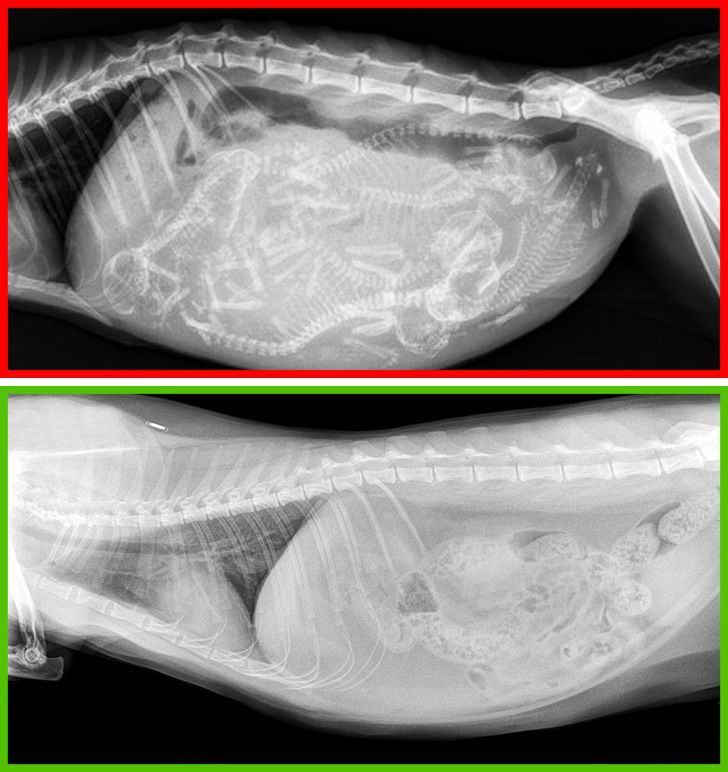

Вверху — рентгеновский снимок беременной кошки, внизу — кастрированного кота.

Эти процедуры в большинстве случаев положительно влияют на организм домашних животных. У кошек снижается риск возникновения рака молочной железы, а у котов — рака яичек. Кроме того, кастрированные коты реже убегают из дома и проявляют агрессию.